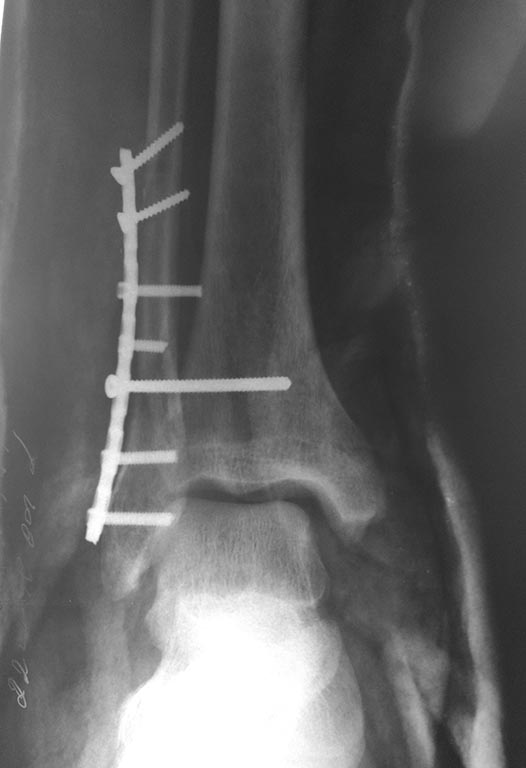

интраоперационно

на следующий день

Перелом несвежий, понимаю. Жаль нет снимка первичного. Не совсем ясен уровень перелома (и его протяженность малоберцовой кости).

Ошибки у Вас интраоперационные -

1 - не восстановлена длина наружной лодыжки, сохраняется укорочение. Поэтому таранная кость смещена латерально и кпереди.

2 - я бы не стал использовать реконструктивную пластину.

3 - Ревизия дельтовидной связки сделана?

Мой вывод - показан реостеосинтез.

Вся беда в том, что снимки в операционной и после с разной ротацией голени. Репозиция нар. лодыжки не гут. Подвывих есть. Перфекционизм требует реостеосинтеза. Ваши действия будут зависеть от возраста, местного статуса, психики пациента и умения убедить без вреда для себя. Пластина не причём. Много лодыжек прооперировали реконструктивными пластинами. Главное репозиция.

Моё мнение, что ничего переделывать не нужно. Подвывиха стопы кнаружи у пациента нет. Есть подвывих кзади, так как пластинка лежит по передней поверхности малоберцовой кости, а синдесмозный винт выталкивает таранку кзади. Может через 2-2.5 мес после операции удалить винт, а может после нагрузки без удаления винта подвывих кзади устранится.

Коллеги! Вы о чем? Лодыжка фактически не фиксирована (1 винт не в счет при таком расположениии пластины). М/б притянута куда-то к передним отделам "позиционником" - если хотите убедиться сделайте КТ и посмотрите сканы через вырезку. Мое мнение - срочно все это разбирать. Синтезировать н/лодыжку пластиной в противоскользящем положении. затем тестировать синдесмоз. А уж потом размышлять - нужно ли его фиксировать и если да - то чем.

Перелом надсиндесмозный. Лодыжка фиксирована все-таки 2 винтами. а вот синдесмозный винт вроде бы стоит уже в переломе и просто прижимает пластину к большеберцовой кости. на счет реостеосинтеза даже не знаю, но вроде бы послеоперационные снимки сделаны с небольшим вальгусом стопы. Есть ли снимки в нейтральной позиции стопы?

Если внимательно посмотреть снимки, один из винтов, удерживающих пластину, совершенно точно упёрся в большеберцовую (он даже полностью не погружён в блокирующее отверстие). Скорее всего он отодвинул фибулу. Позиционный винт лишь зафиксировал такую позицию. Можно поменять винт на короткий и перепровести позиционный малоинвазивно, ИМХО. С уважением!

Комментировать остеосинтез не буду. Но просто хочу напомнить, что существует такой инструмент как измеритель глубины каналов. ,,Позиционник'' не должен ничего прижимать. Положение пластины на малоберцовой кости в этом случае желательно - заднее (опорная, противоскользящая) Не знаю, делался ли hook test? В моем видении передняя межберцовая связка д.б. цела -по характеру линии перелома наружной лодыжки. В этом случае зачем позиционный винт? Был ли поврежден медиальный комплекс (порции дельтовидной связки)? Надо ли что-то сейчас делать? Не знаю. Надо взвесить много факторов. Желаю удачи авторам в общении с пациентом.T

Я бы переделал. Считаю, что подвывих есть. Наружная лодыжка сильно короткая и находится совсем не в своей вырезке (отсюда и передний ещё подвывих). Гипсом (как на последнем снимке) ситуацию не выправишь, потому что гипс когда-нибудь придётся снять, и всё вернётся, куда и должно, в соответствии с биомеханикой. Верить в то, что с удалением винта всё станет на свои места, я бы тоже не стал. Такое возможно при передавливании синдесмоза, да. Но тут совсем другие проблемы. Если у Вас всё ещё есть сомнения, сделайте КТ - и всё увидите.